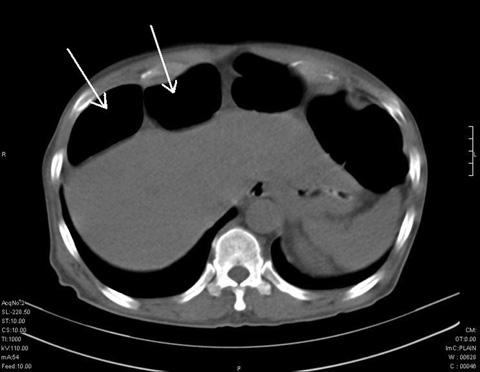

A chest x-ray revealed hepatodiaphragmatic interposition of the large bowel (Chilaiditi sign). Abdominal computed tomography confirmed the presence of bowel loops anterior to the liver (Figures, arrows) and grossly dilated large bowel with no evidence of pneumoperitoneum. Biochemical analysis revealed hyponatraemia and hypokalaemia.